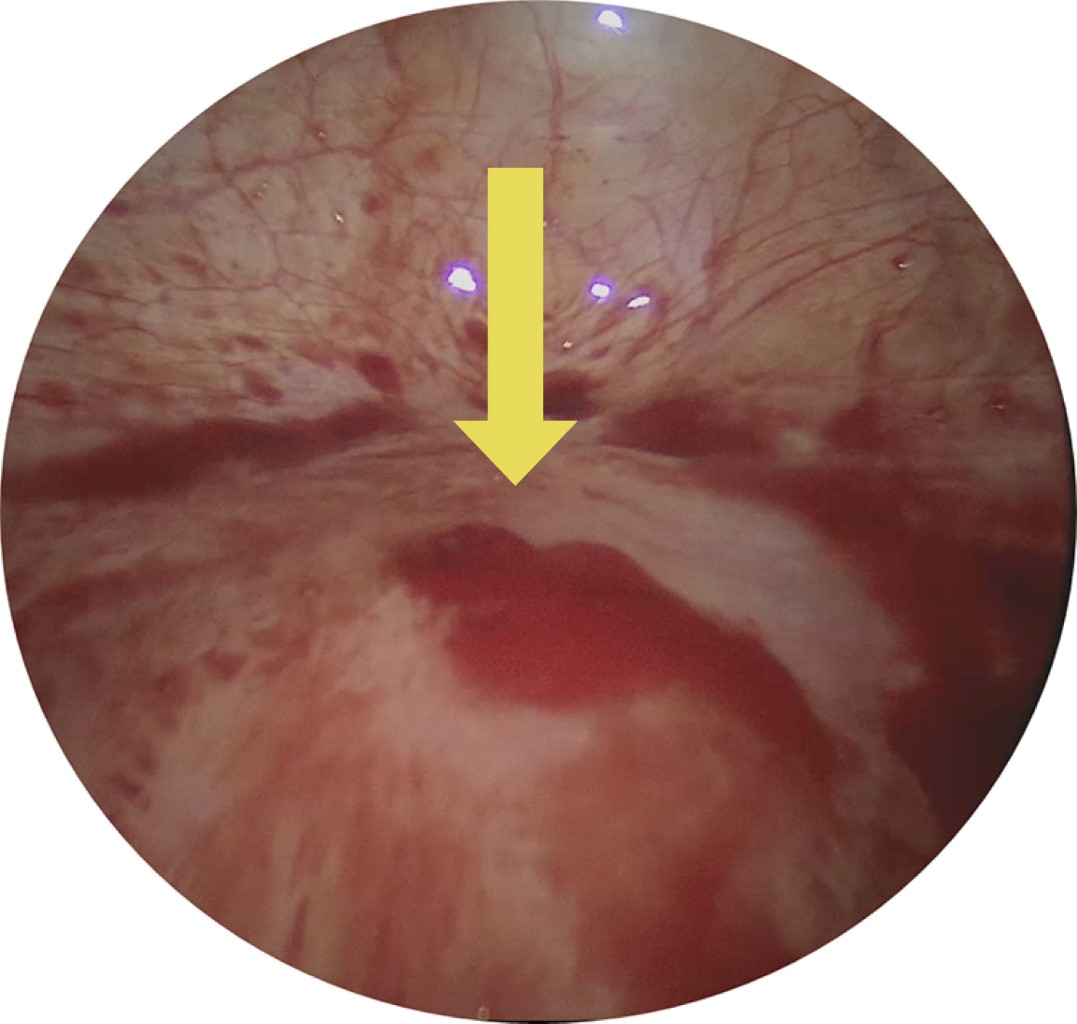

Debido a estos hallazgos, la paciente fue sometida a laparoscopía exploradora en donde se evidenció hemoperitoneo de 2,000 cm3 que fue aspirado (Figura 2) y una lesión de 5 mm de diámetro en la cara anterior del fondo uterino como origen de la hemorragia (Figura 3). Se procedió a realizar cierre hemostático utilizando sutura absorbible 2-0 (Figura 4), la paciente tuvo una evolución favorable, tolerando vía oral de manera temprana, con signos vitales dentro de parámetros normales durante todo su internamiento y sin requerimiento de transfusión de hemoderivados, fue dada de alta del servicio al cumplir 24 horas de estancia intrahospitalaria.

Figura 3